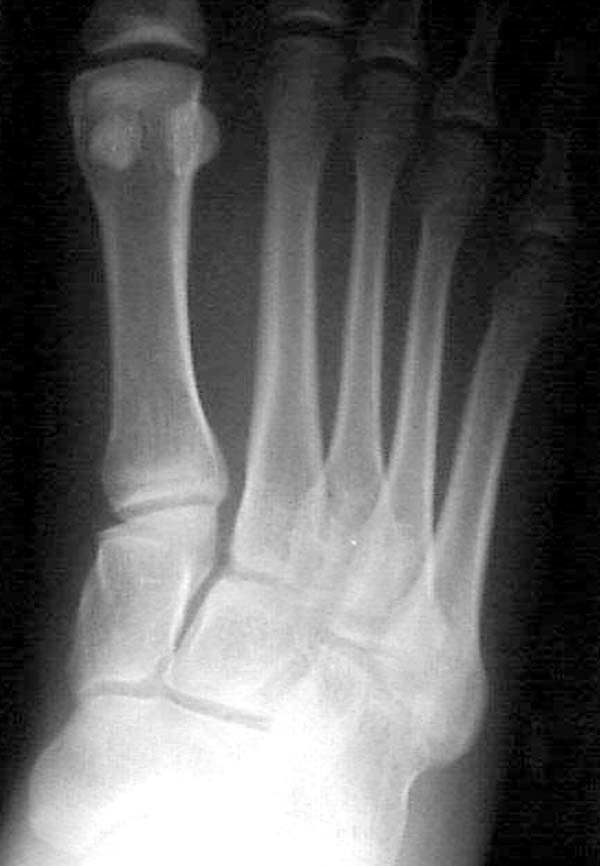

Здесь КТ и сравнительные снимки стопы под нагрузкой.

Диагностировано повреждение медиальной и латеральной колонны.

Если оперативное лечение - как и каким доступом?